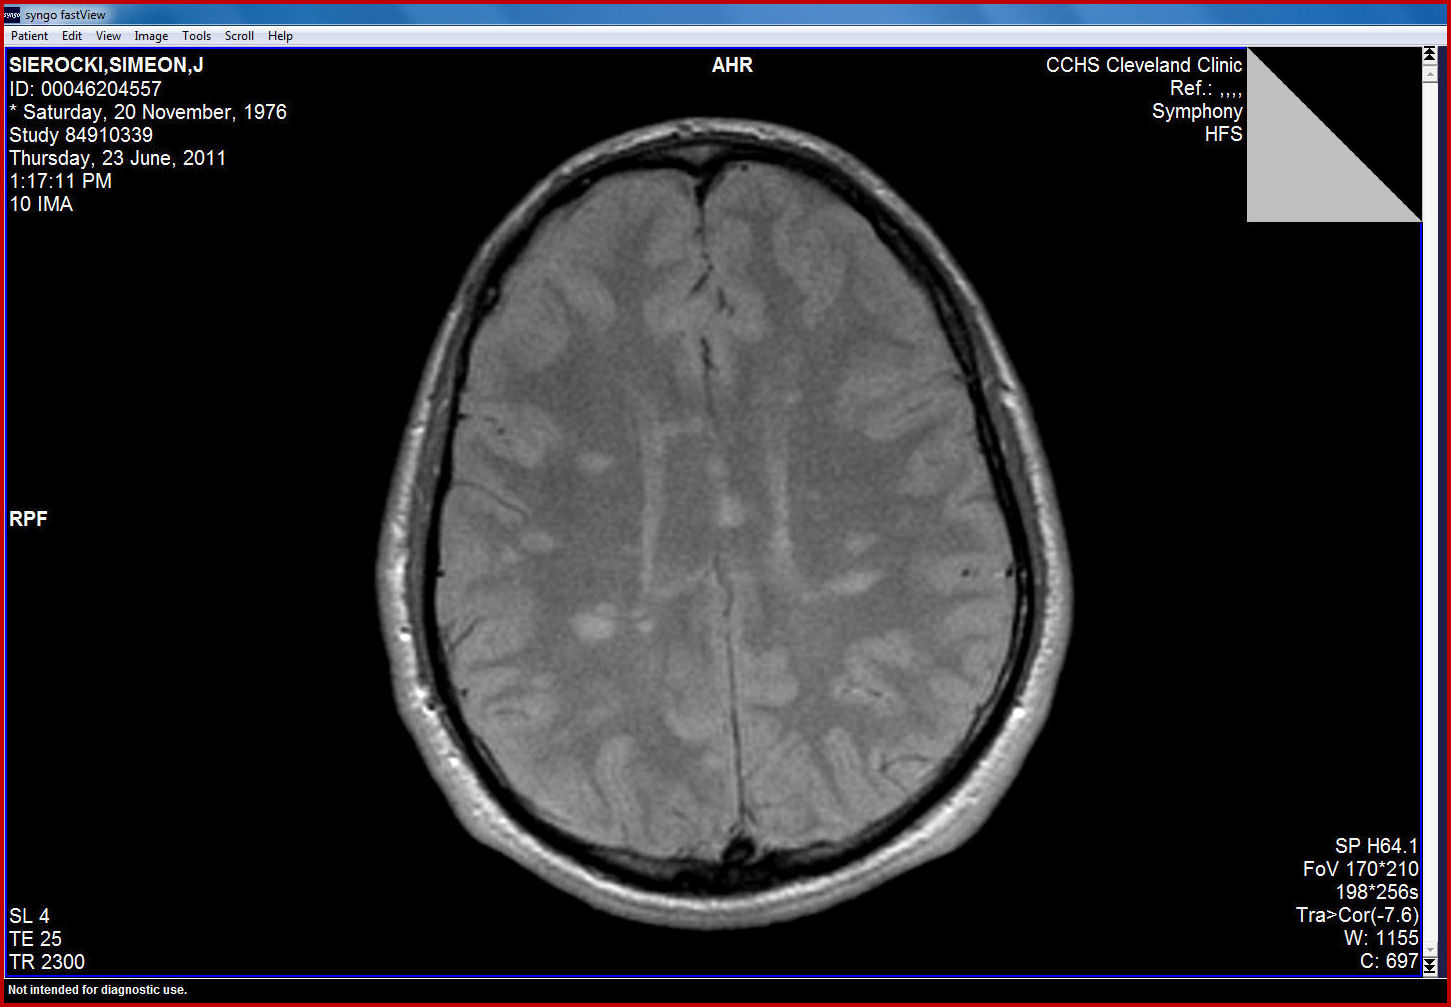

Viral encephalitis: a clinician’s guide l JC/BK* virus (causes progressive multifocal leukoencephalopathy) In immunocompetent patients T2-weighted MRI brain scan showing right temporal lobe hyperintensity in a patient with herpes encephalitis ... Access Doc

BK Virus-Associated Progressive Multifocal Leukoencephalopathy . Jennifer Chu, M.D. 1, Samish Dhungana, MRI of the brain showed asymmetric diffuse the brain was unchanged from before. JC virus PCR remained negative. ... Read Content

Ring Enhancing Lesions in a Patient with AIDS Jonathan Waks, Harvard Medical School Year III (JC virus) • Bacterial • Fungal 3. Neoplasm T1 MRI of the brain shows an inhomogeneously enhancing lesion ... View Full Source

Running head: Diffusion imaging of PML in HIV activation of the JC virus, The white matter damage can be visualized on standard magnetic resonance imaging (MRI), particularly using acquisition sequences sensitive to white matter alterations ... Read Document

Vol. 27 No. 1 JC Virus DNA Detection in PML:- Arun-ngamwong T & Sungkanuparph S. 23 23 Original Article JC Virus DNA Detection in Cerebrospinal Fluid of AIDS Patients with Progressive Multifocal and/or MRI of the brain showed asymmetric, ... Read Full Source

JC virus (JCV) infection of oligodendro-cytes causes demyelination in brains of patients with with progressive multifocal Wiscott-Aldrich syndrome.Brain MRI showed multiple tiny spots of Gd-DTPA enhanced lesions on a T1 weighted image. Pathological findings for a brain biopsy were patchy, demy- ... Retrieve Content

Symptoms and/or new brain lesions on MRI. C ases of asymptomatic PML based on MRI and positive JC virus DNA in the CSF have been reported. • If PML is suspected, the MRI protocol should be extended to include contrast-enhanced T1- ... Fetch Full Source

Chain reaction for JC virus from the CSF returned positive. Magnetic resonance imaging of the brain showed white matter abnormalities consistent with progressive Hiv-negative Patient following treatment with rituximab Shafik Khoury MD1, Shirley Shapira MD 1, ... Fetch Here

A case of progressive multifocal leukoencephalopathy (PML): diffusion-weighted MR imaging findings weighted MRI. Case Report A 32- year- old man with human immunodeficiency virus system (CNS) caused by neurotropic papova virus (JC polyoma virüs) [1, 2]. PML was originally described in ... View Document